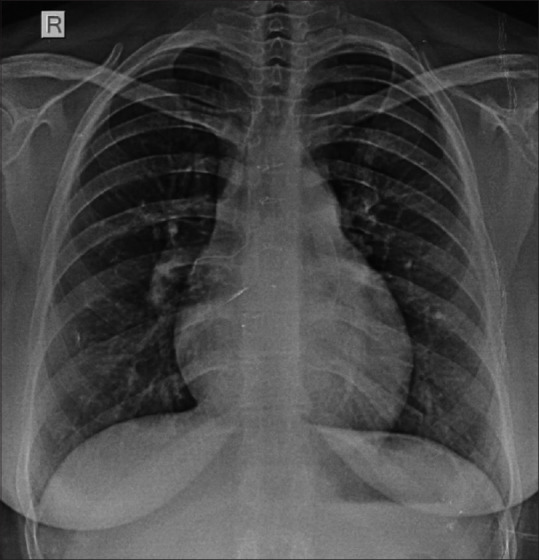

This hemodynamic round section deals with severe pulmonary arterial hypertension with suprasystemic pulmonary artery pressures in a patient who underwent delayed surgical correction of the double-outlet right ventricle with a large subaortic ventricular septal defect (VSD). Recreation of a moderate-sized VSD by electrocautery-aided fenestration of the surgical patch resulted in effective right ventricular decompression. The changes in the hemodynamics are illustrated in the pressure traces and Doppler echocardiographic images. The changes in cardiac events on the right and left heart due to the right bundle branch block are also illustrated in the manuscript.